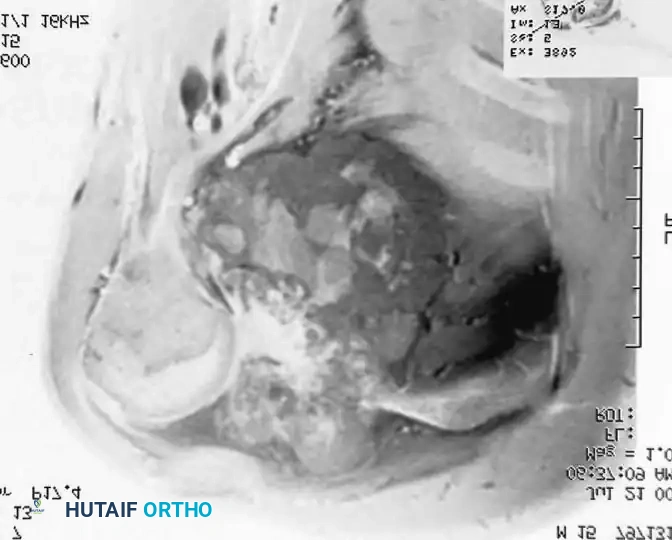

Intraoperative Imaging and Margin Assessment

Continuous intraoperative assessment using fluoroscopy and frozen section pathology is mandatory. The following images demonstrate various stages of complex upper extremity resections, allograft preparations, and prosthetic implantations across the humerus and elbow joint.

Distal Humerus and Elbow Reconstruction

When tumors involve the distal humerus, resection often requires sacrifice of the collateral ligaments and the articular surface of the elbow. Reconstruction is typically achieved using a linked, semi-constrained total elbow arthroplasty designed for oncologic defects.